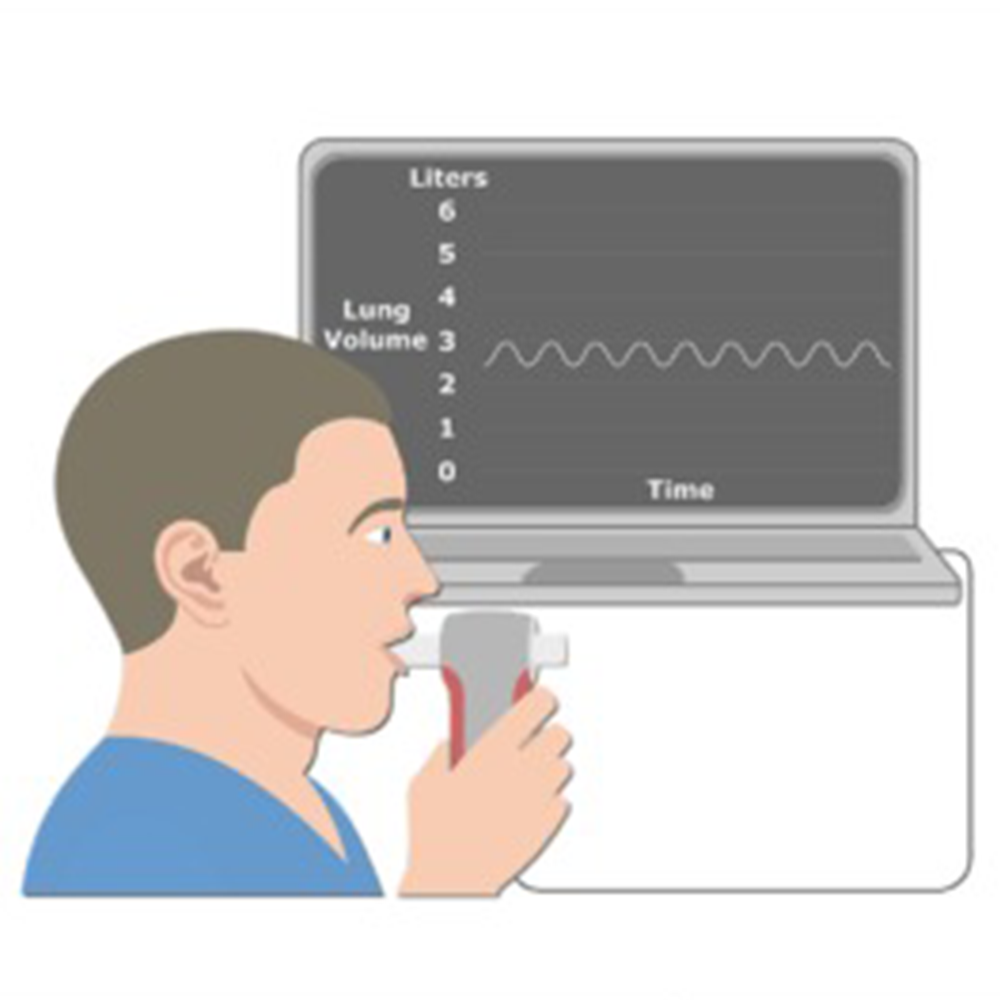

Lung Functions Testing

Lung Functions Testing